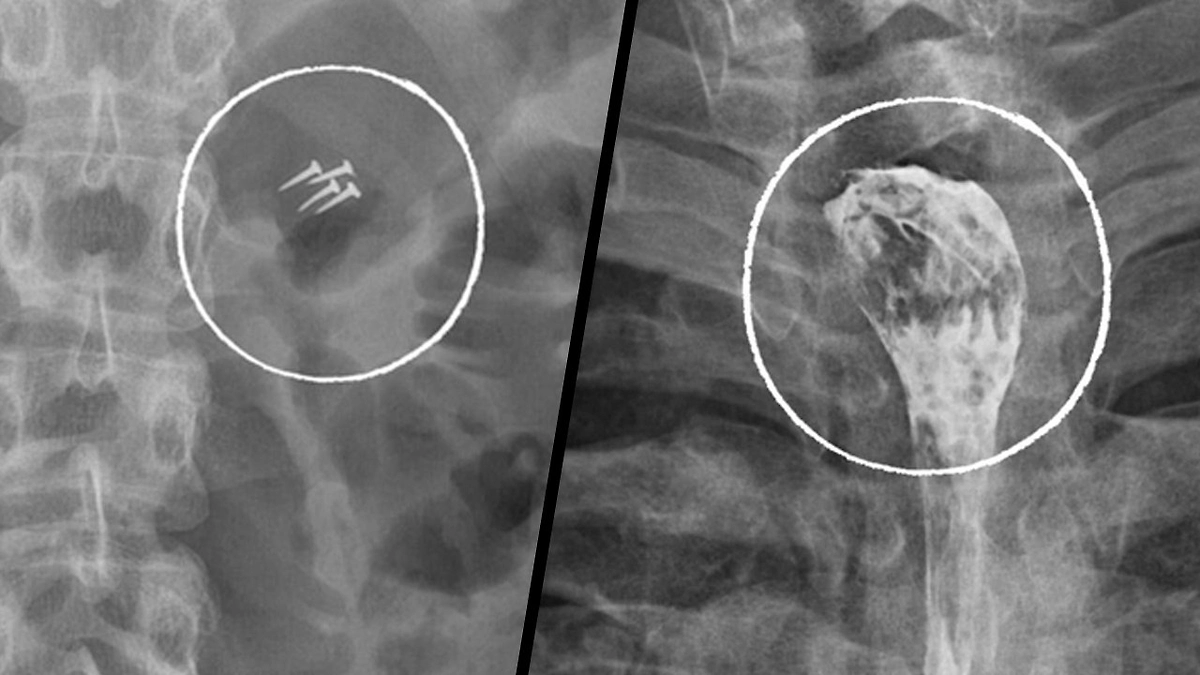

НИИ скорой помощи имени Н. В. Склифосовского опубликовал подборку самых необычных предметов, которые врачи извлекли из пациентов в 2025 году. Список появился в Telegram-канале медицинского учреждения.

За год медикам пришлось удалять беспроводные наушники, зубные коронки, абрикосовую косточку, черенок ложки, украшения и даже гвозди, которые пациенты случайно проглотили, в том числе во время ремонтных работ.

В клинике отметили, что такие случаи выглядят курьёзно, однако остаются серьёзной проблемой. Ежегодно в Склиф поступают десятки пациентов с инородными телами в организме, которым требуется экстренная помощь, а в некоторых случаях — длительное восстановление после хирургического вмешательства.